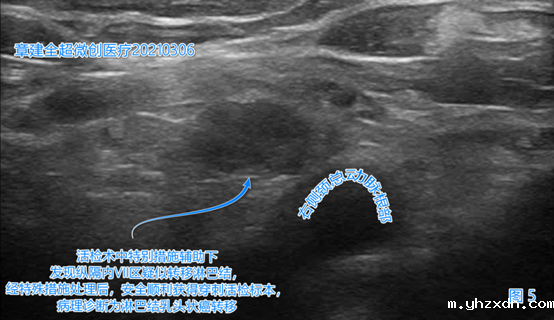

左侧颈部VI(6)区(图4)、

右侧颈部VI(6)、右侧颈部VII(7)区(图5)出现了疑似癌转移的淋巴结。